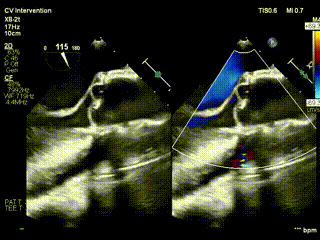

视频4:病例2 术后无反流

视频3:病例2术前心超提示大量主动脉瓣反流